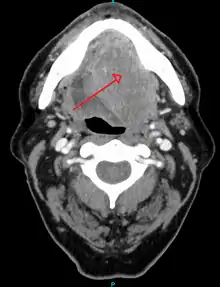

Head and neck cancer

About 90%[4] of cases of head and neck cancer (cancer of the mouth, nasal cavity, nasopharynx, throat and associated structures) are due to SCC.